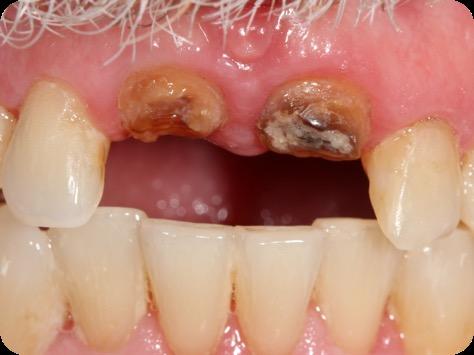

This case was performed by Dr Homa Zadeh, DDS, PhD, a respected leader in periodontology and implant dentistry. Dr Zadeh’s approach emphasizes biologically driven protocols and evidence-based techniques, making this case a strong example of clinical excellence using the Tapered Pro Conical system. It involves the replacement of two front anterior teeth after they fractured off and the full restoration process.

Fig 1. Patient anterior situation. Two anterior crowns fractured off.

Fig 2. Intraoral radiograph indicating tooth structural loss extent.